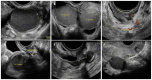

Figures